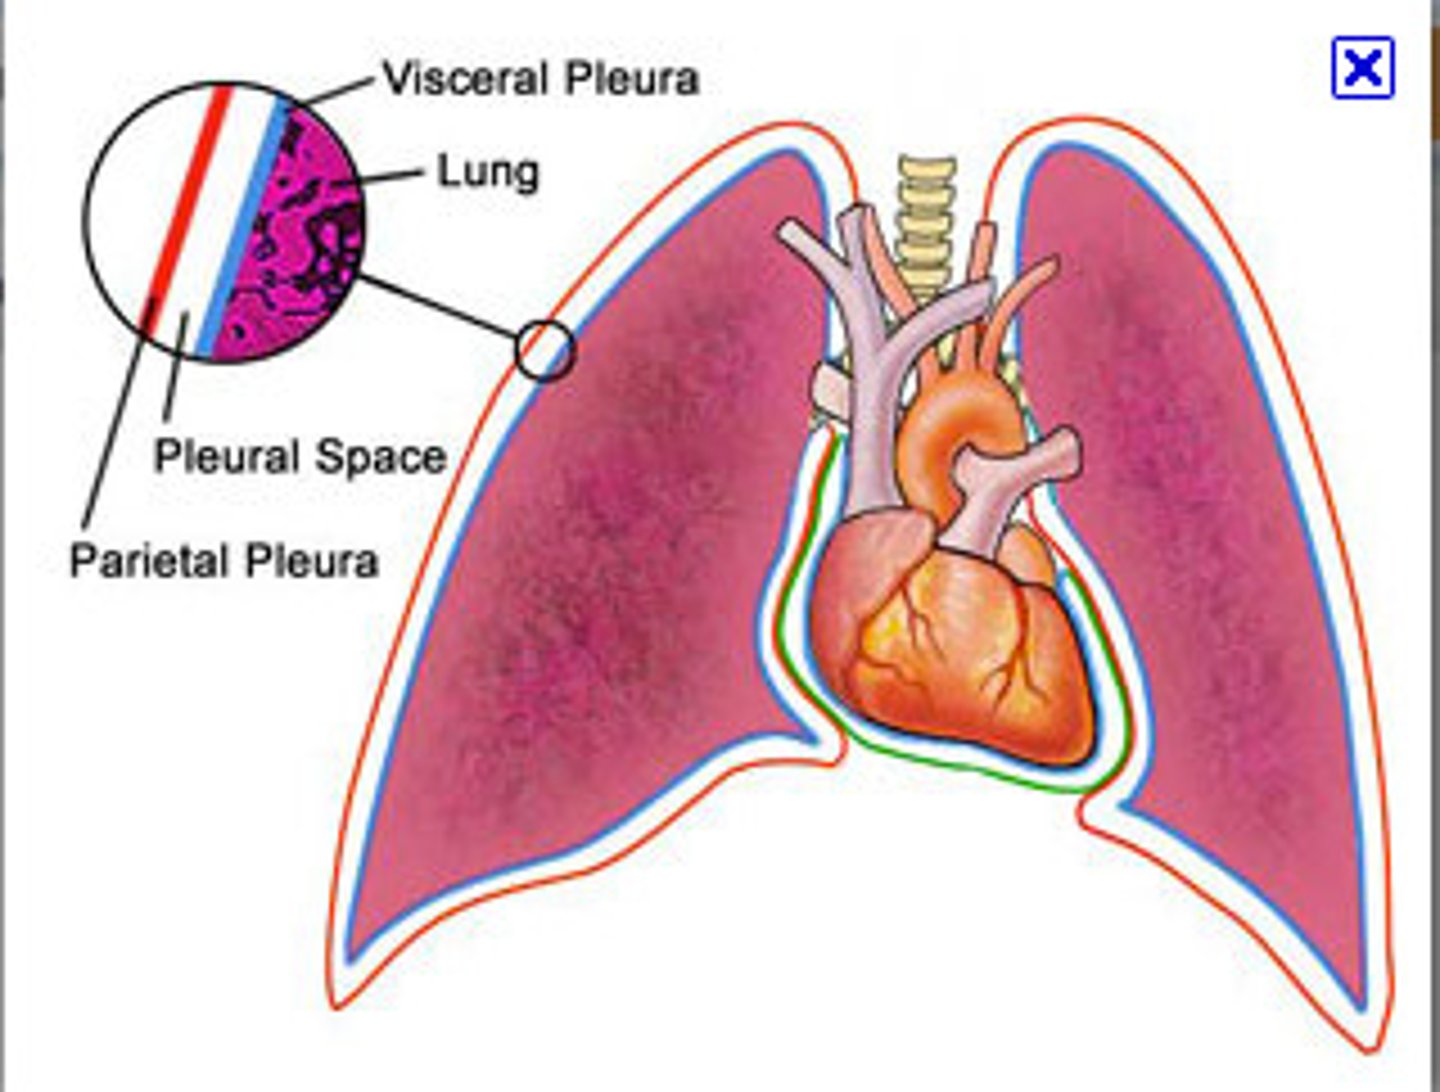

pleurae

parietal pleura

outermost layer of the pleura that connects to the thoracic wall, mediastinum, and diaphragm

visceral pleura

innermost layer of the pleura that is superficial to the lungs and extends into the lung fissures

pleural cavity

space between the visceral and parietal pleurae

pleural fluid